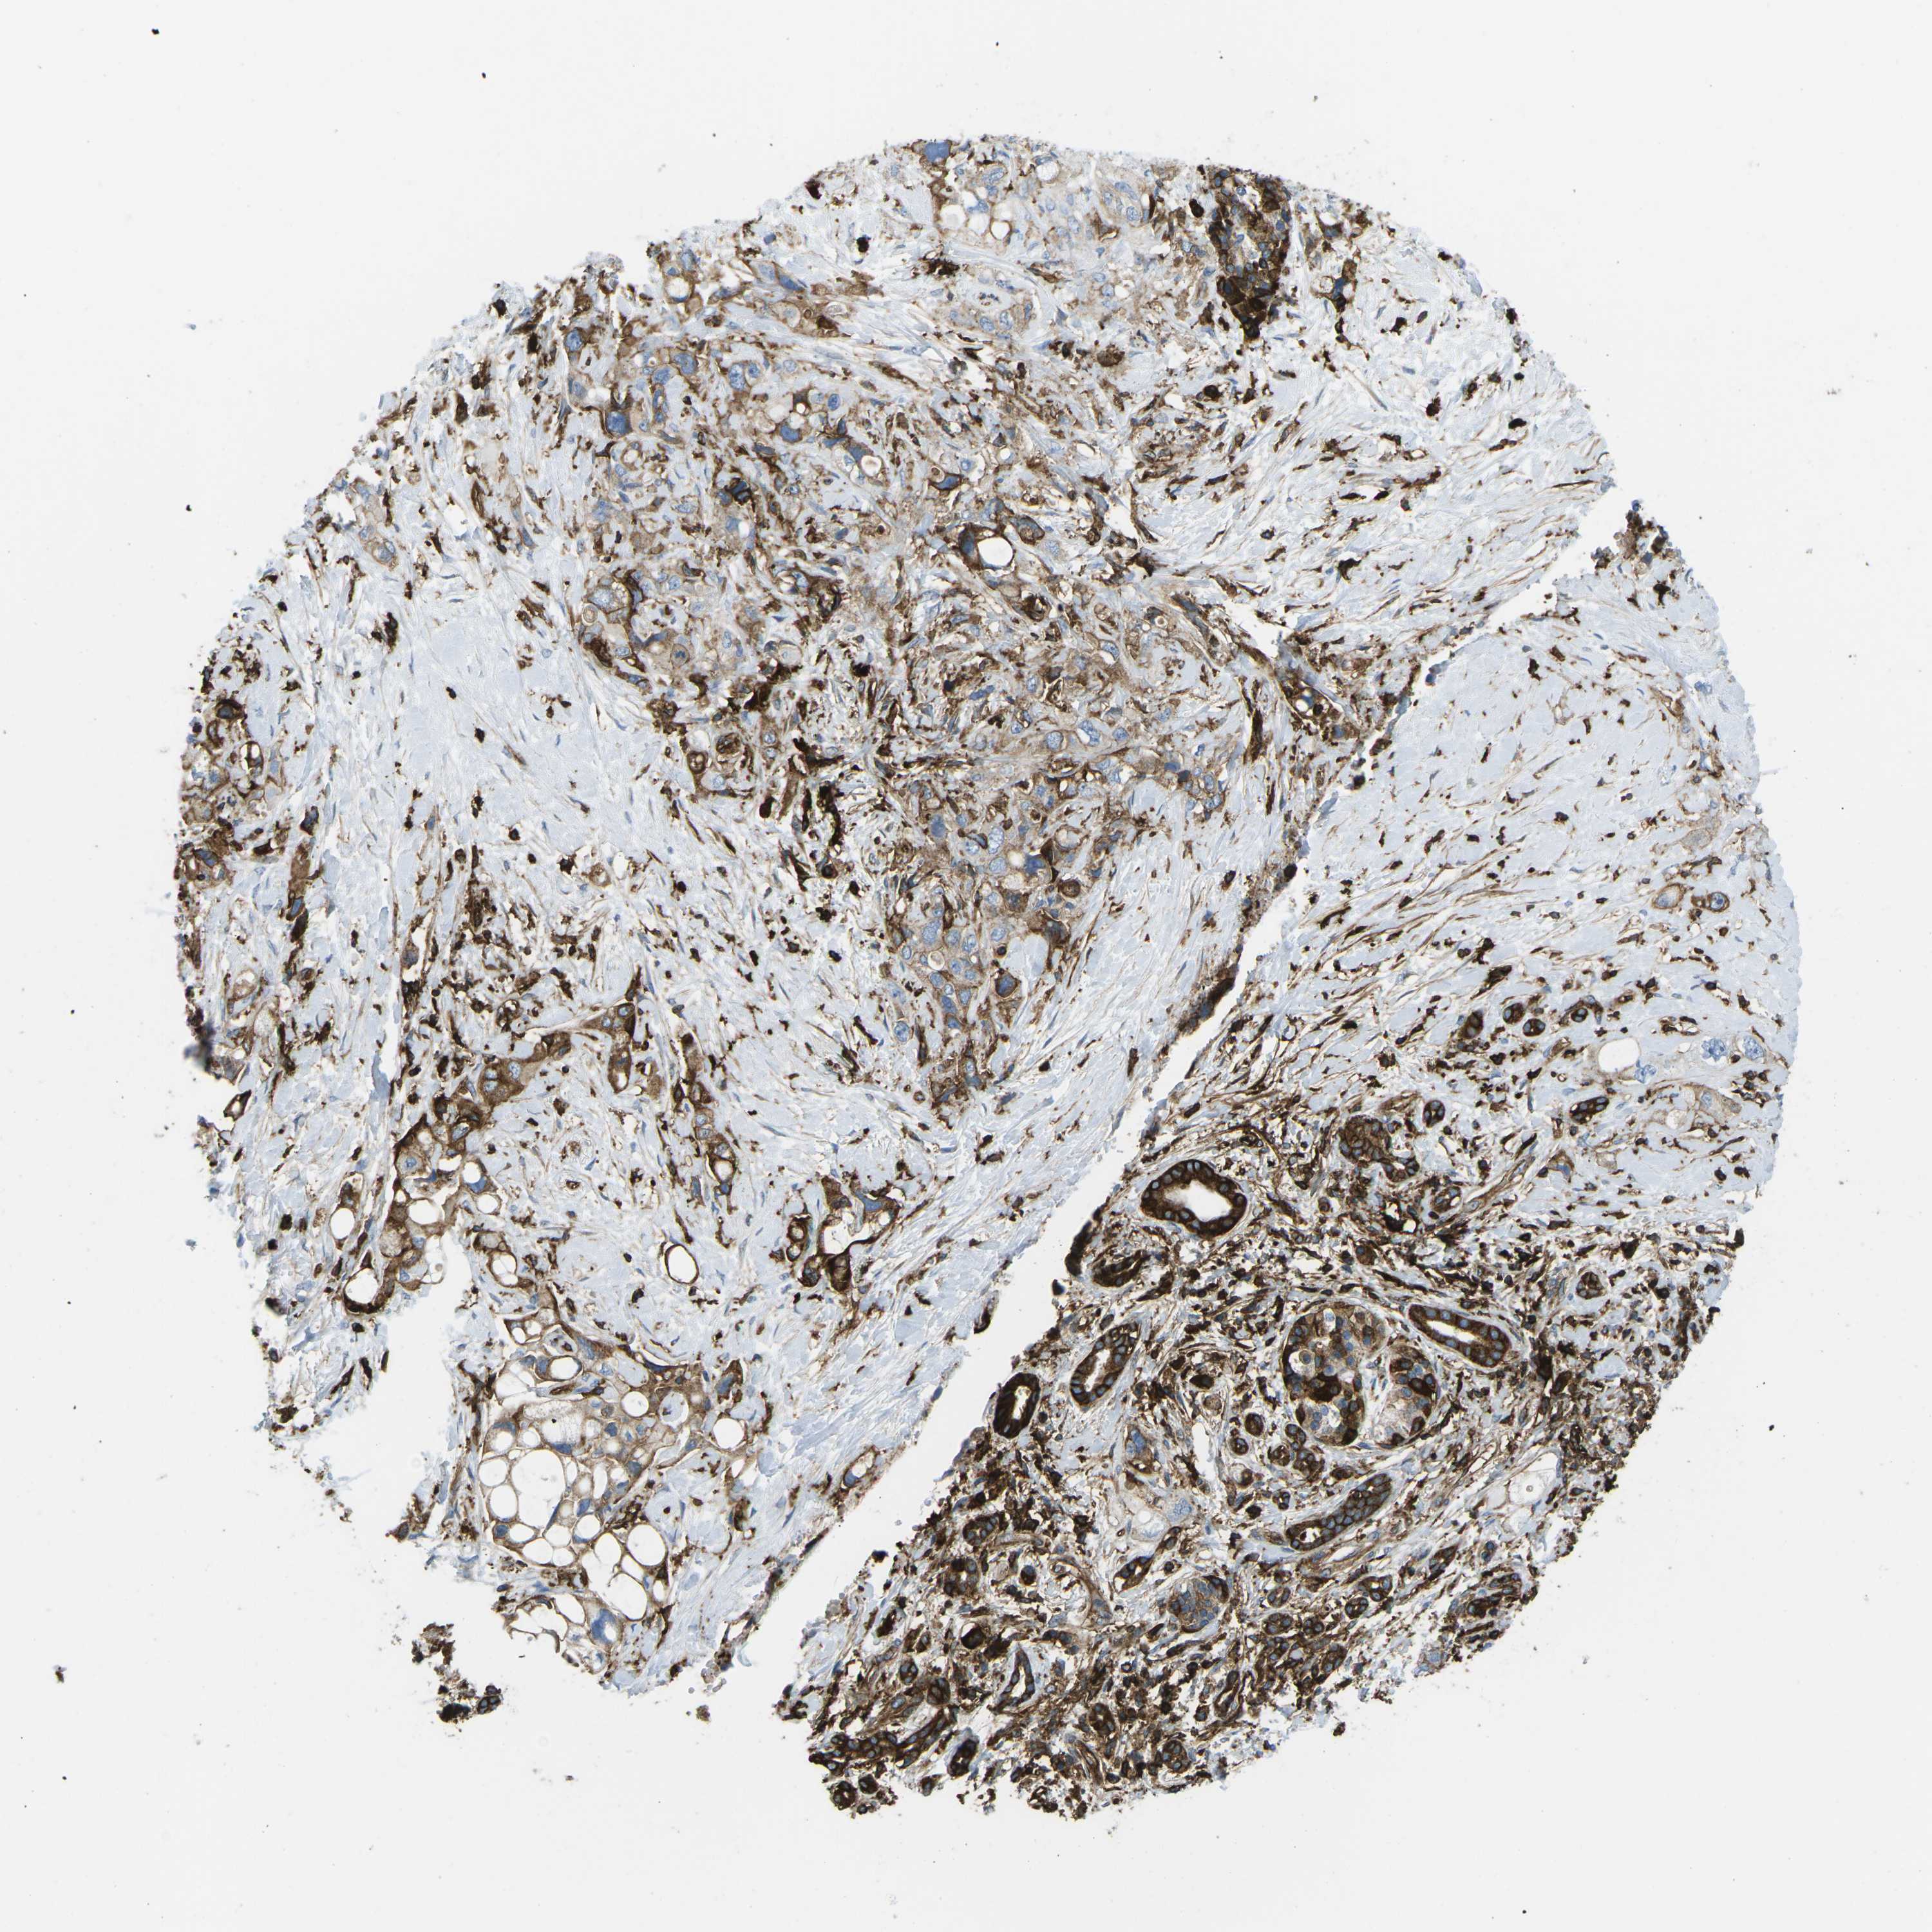

PANCREATIC CANCER - Protein expressioni

A mouse-over function shows sample information and annotation data. Click on an image to view it in a full screen mode. Samples can be filtered based on level of antibody staining by selecting one or several of the following categories: high, medium, low and not detected. The assay and annotation is described here.

Note that samples used for immunohistochemistry by the Human Protein Atlas do not correspond to samples in the TCGA dataset.

Antibody stainingi

Antibody staining in the annotated cell types in the current human tissue is reported as not detected, low, medium, or high, based on conventional immunohistochemistry profiling in selected tissues. This score is based on the combination of the staining intensity and fraction of stained cells.

Each image is clickable and will lead to virtual microscopy that enables deeper exploration of all samples and also displays staining intensity scores, fraction scores and subcellular localization as well as patient and tissue information for each sample.

Antibody CAB015418

Staining

High

Medium

Low

Not detected

Intensity

Strong

Moderate

Weak

Negative

Quantity

>75%

75%-25%

<25%

None

Location

Nuclear

Cytoplasmic/membranous

Cytoplasmic/membranous,nuclear

Adenocarcinoma, NOS